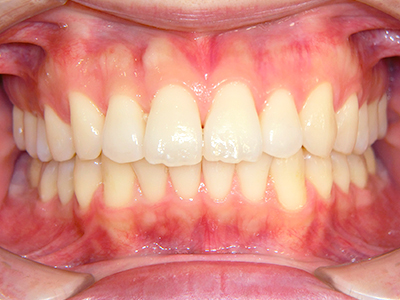

ないき歯科クリニックでは、上あごの成長不足を補い、鼻呼吸を獲得しつつ歯列を整え、将来のお口をより健康な状態にすることをゴールに定める矯正治療をおこなっています。

【4】矯正治療

矯正装置を装着し、調整しながら少しずつ歯を移動させ、歯並びを整えていきます。

状態によって家庭でのトレーニングが必要な場合もあり、治療期間も個人差があります。

あくまでも平均値ではありますが、一般的には月1回程度来院頂き、1~2年程度を目安に治療を進めていきます。